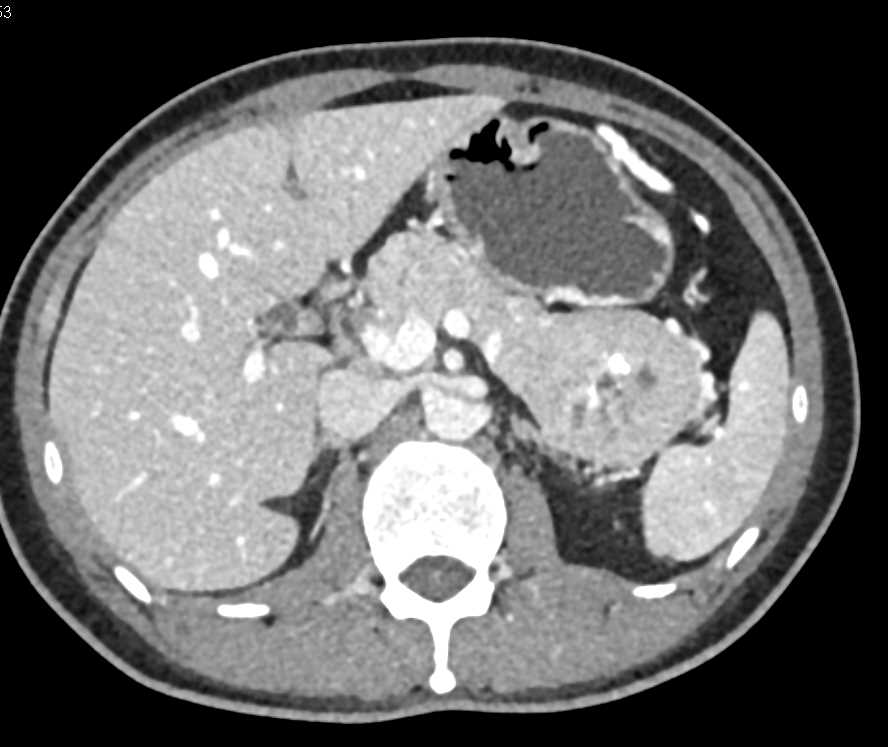

PNET Tail of the Pancreas